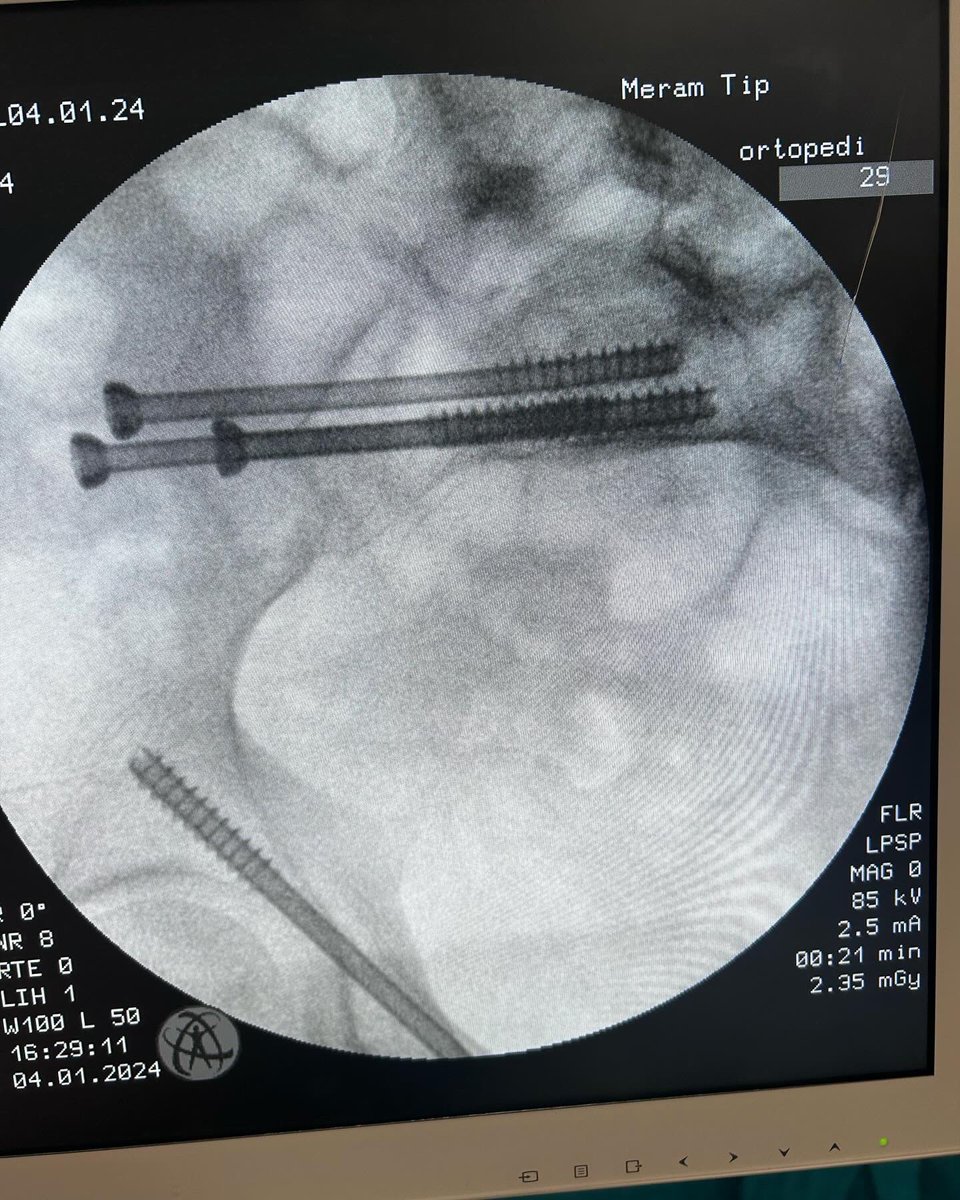

Male 40yo, healthy and physically active.

How do you treat this fracture?

Nonop, ORIF with plate or nailing?

@InvictaOrtho @traumaticum @rkh_md @Gnomelover1970 @aqueipot @DrMarecek

@DrBhavinJadav

#orthotwitter